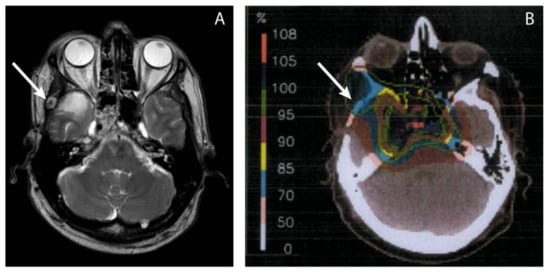

| 5 | Clivus |

| Proton / Photon | Ala minor os sphenoid Subcutaneous preauricular Frontal bone Subcutaneous frontal Dura mater frontal right | 41 | Surgery Photon radiotherapy (Linac) |